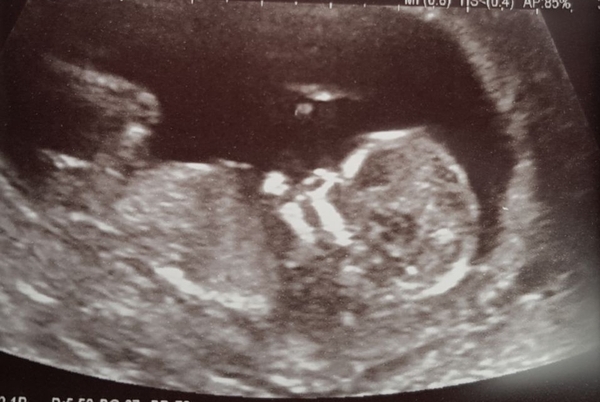

I had my 12 week scan today. Baby is all healthly and date been pushed back 2 days so I'm due 7/6/18 and I'm now 13W+4D. I hope everyone feeling Ok?

Great pic mummyloves... 😁